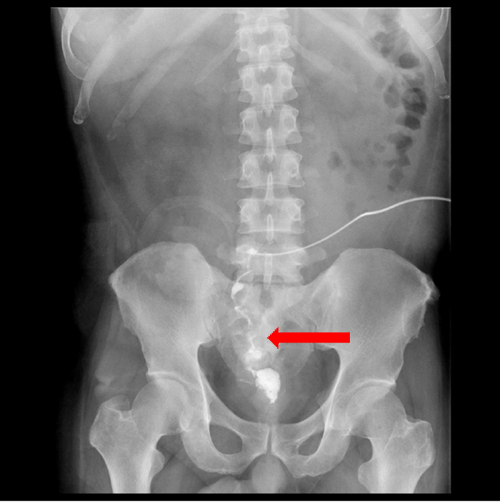

Fluoroscopic image showing injection of 33 n butyl cyanoacrylate glue... Download Scientific Cyanoacrylate Glue Injection temporizing measures to halt active bleeding are often not the definitive treatment of choice to prevent rebleeding from gv, whereas definitive measures such as endoscopic cyanoacrylate injection (eci) or endovascular treatments are often not feasible in the acute, diagnostic setting. under endoscopic guidance, a liquid monomer called cyanoacrylate glue is injected via a needle into the varix. . Cyanoacrylate Glue Injection.